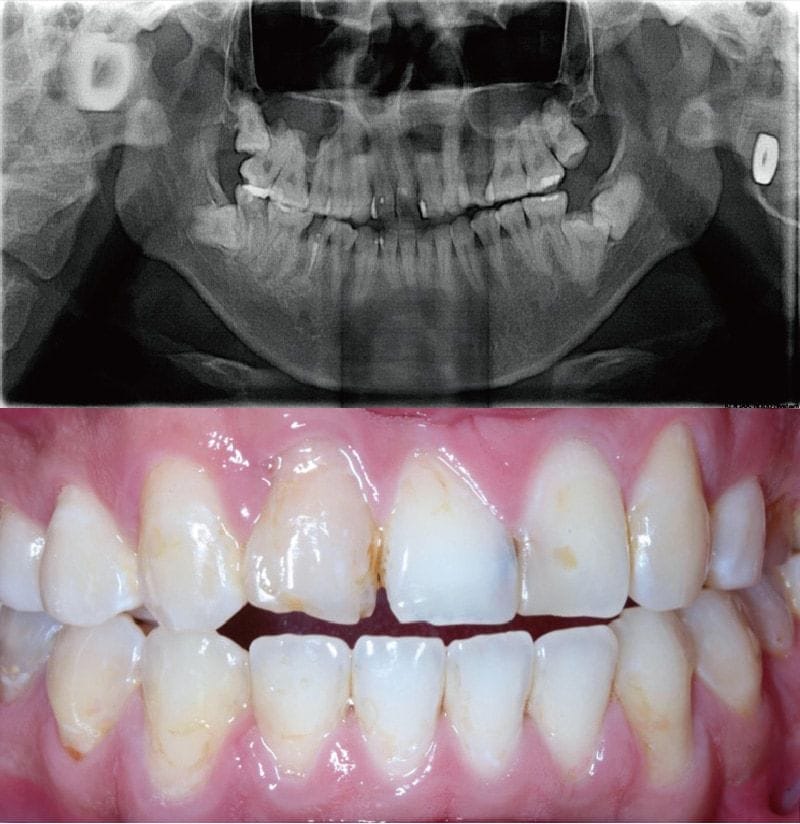

圖示:療程前Mr.Su前牙美觀區域的環口式X光片與口內檢查對比照

而從口內檢查和環口式的X光片對照,發現Mr.Su蛀牙率很高。

早年因曾有唇顎裂經過修補與全口齒顎矯正治療,上顎兩顆缺牙在矯正後空間都已經關閉。只不過針對前牙美觀區域,除了蛀牙方面的修補,我們認為能夠透過陶瓷貼片和數位牙科的技術,會在視覺上改善,顏色和材料也能長期穩定耐用。

圖示:療程前Mr.Su的前牙美觀區牙齒近照,葉醫師建議以陶瓷貼片改善牙齒顏色、長度等美觀問題